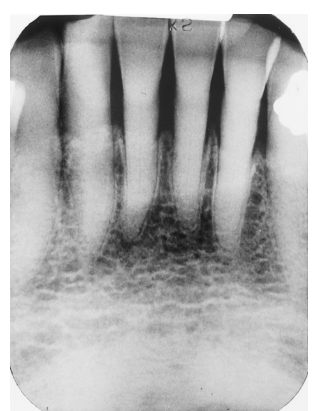

This patient is a 72-year-old man. Notice that the pulp and root canal spaces are significantly diminished. What is the cause of this?

attrition and age